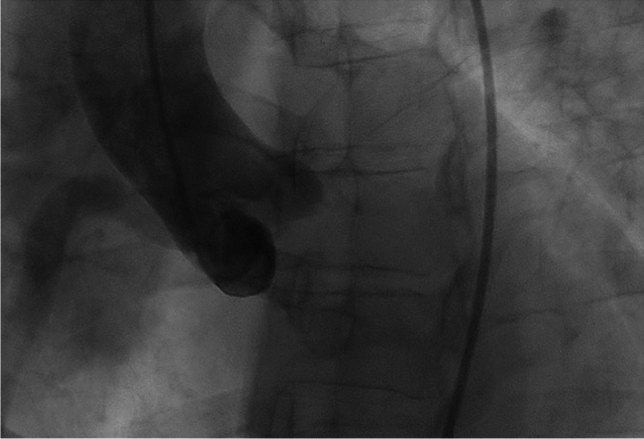

A 39-year-old women with newly diagnosed ALCAPA syndrome during pregnancy.